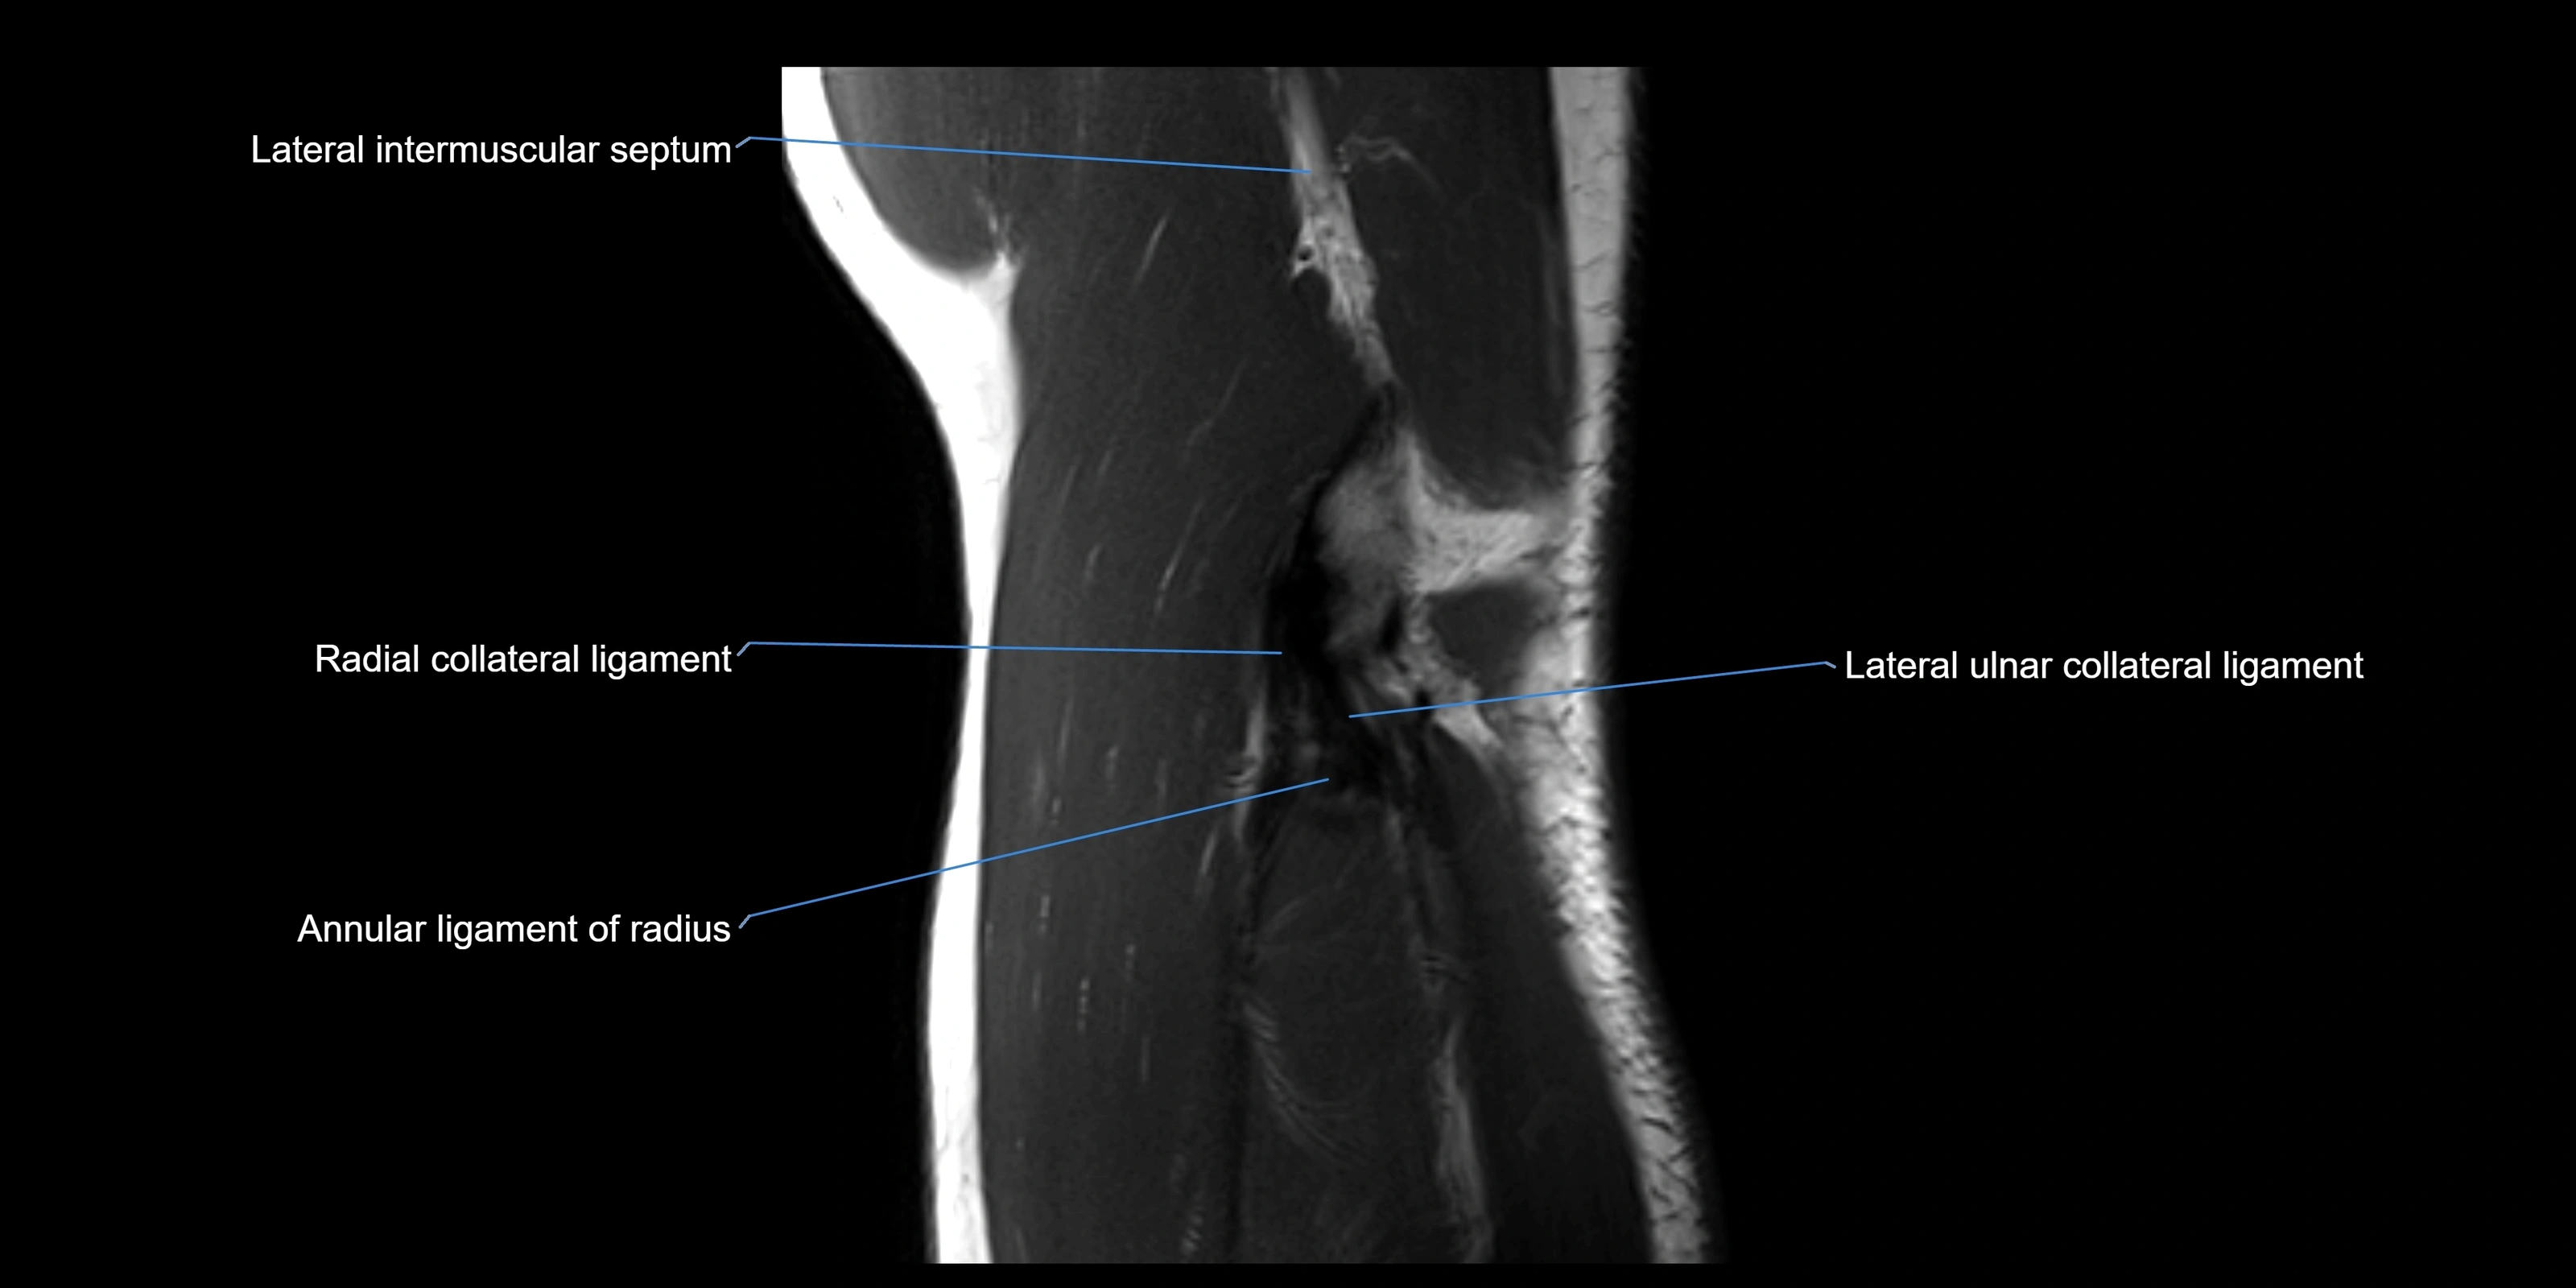

Annular ligament of radius

The annular ligament of the radius is a strong, circular band of fibers that encircles the head and neck of the radius, holding it securely against the radial notch of the ulna. It forms part of the proximal radioulnar joint, permitting smooth rotation of the radius during pronation and supination of the forearm.

The ligament acts like a collar or loop, maintaining radial head stability while allowing rotation. It is essential for forearm motion, elbow stability, and load transmission from the radius to the ulna and humerus.

Origin, Course, and Insertion

• Origin: Arises from the anterior margin of the radial notch of the ulna.

• Course: Forms a strong circular band that wraps around the radial head and neck, maintaining them within the radial notch.

• Insertion: Attaches to the posterior margin of the radial notch, completing a fibrous ring around the radial head.

• The inner surface of the ligament is lined with synovial membrane, allowing frictionless rotation.

Relations

• Superiorly: Blends with the capsule of the elbow joint.

• Inferiorly: Supported by the quadrate ligament at the neck of the radius.

• Medially: Attached to the ulnar radial notch.

• Laterally: In contact with the radial head and its articular cartilage.

• Anteriorly: Related to the radial collateral ligament of the elbow.

• Posteriorly: Continuous with the elbow joint capsule.

MRI Appearance

T1-weighted images:

• Ligament: low signal intensity (dark), appearing as a continuous band around the radial head.

• Adjacent fat and marrow: bright, creating contrast with the ligament.

• Thickening or disruption indicates injury or fibrosis.

• Joint capsule and synovium seen as thin low-signal lines contiguous with ligament margins.

T2-weighted images:

• Ligament: low signal (dark) with clear delineation from joint fluid.

• Fluid or edema: bright hyperintense, separating or surrounding the ligament in partial tears.

• Complete tear: discontinuity or non-visualization of ligament fibers, often with joint effusion.